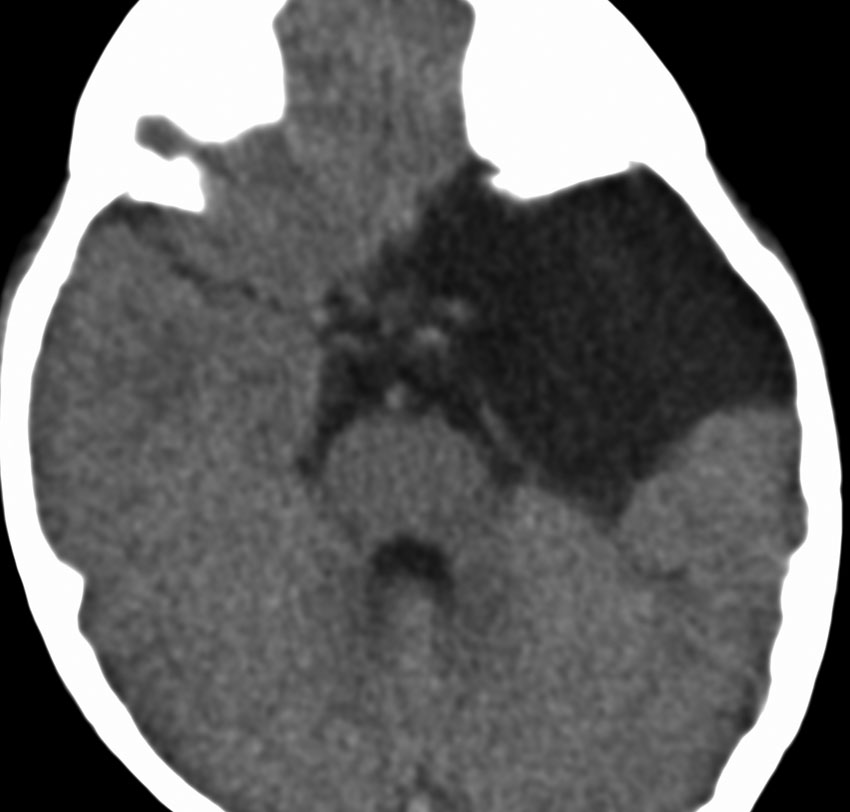

くも膜のう胞が脳室内にできて,脳室の一部で髄液の流れをさまたげて,部分的な水頭症になることがあります。水頭症になっても停止性水頭症というもので悪化傾向がなければ治療の必要がありません。多くは側頭角というところが拡大するのですが,拡大傾向がはっきりしたら,内視鏡手術でくも膜のう胞の壁を切除します。

これは11歳の子供で偶然発見された右側脳室くも膜のう胞です。無症状で変化しませんからほっておきます。右のモンロー孔に狭窄があるために右側脳室だけの停止性水頭症になっています。